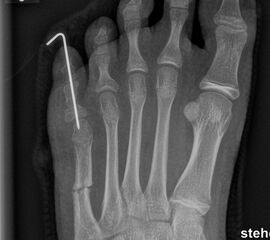

Schneiderballen: MT V Osteotomie

Diese Osteotomie ist indiziert bei stark lateralisierten MT V Köpfchen wie es nicht selten in Kombination mit einem Hallux valgus, einem Ballen-Hohlfuß oder Klumpfuß vorkommt (Abb. 25).

Dementsprechend führen wir die MT V Osteotomie häufig als Kombinationseingriff durch. Sie kann subcapital im Sinne der Kramer-Osteotomie oder adduzierend am Schaft durchgeführt werden (Abb. 26).

Abb. 26 a-e: adduzierende Osteotomie. (a) Fuß präoperativ d.p. und (b) als Schrägaufnahme. Im Schrägbild gut sichtbar die subluxierte 5. Zehe. (c) intraoperative Aufnahme der MT V Schaftosteotomie. (d) Fuß postoperativ d.p. und (e) als Schrägaufnahme.